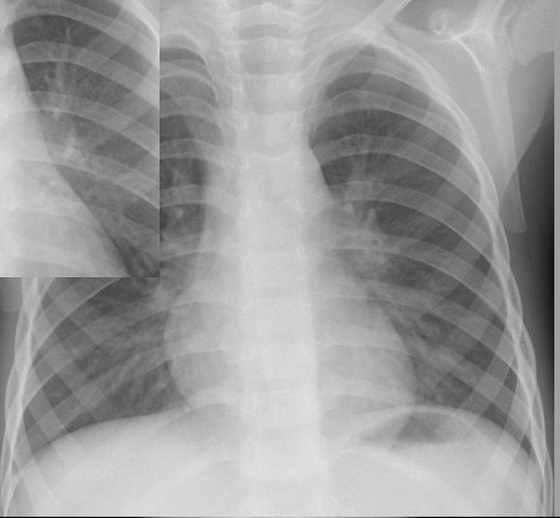

肺門部の浸潤影はいつも慎重に判断する必要がある。下写真の左肺門部の心陰影ははっきりせず(左上挿入写真は治癒時)判断に迷うがシルエット陽性と判断すればS6もしくはS3の肺炎が推定可能になる。下の写真はS6の浸潤影が想定される。